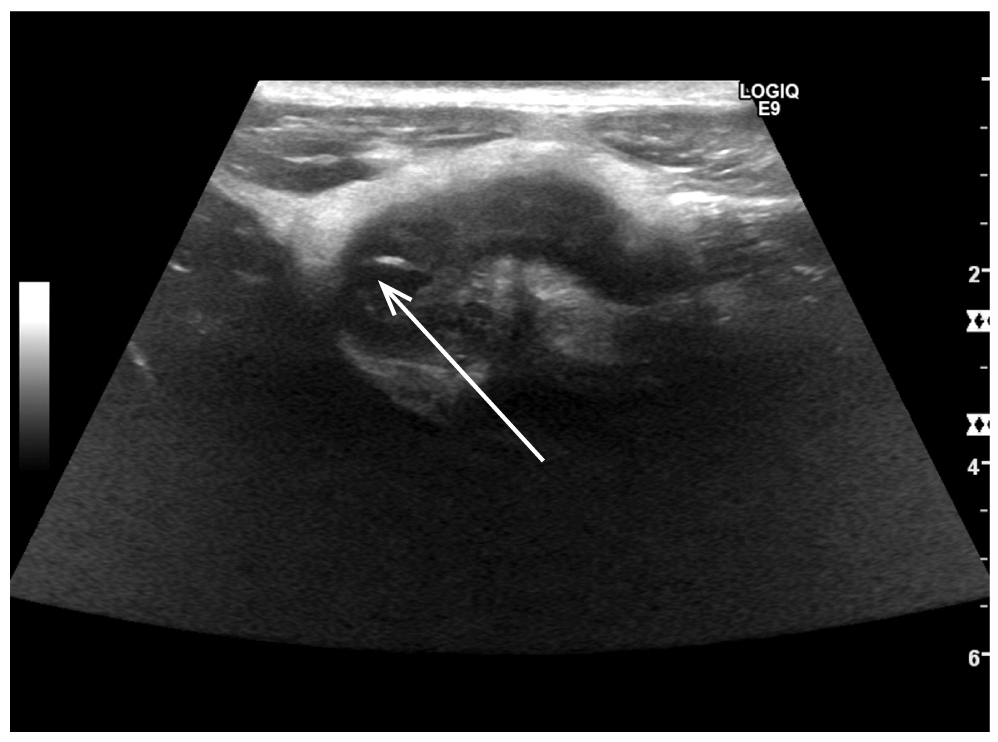

Предоперационная программа обследования включала физикальный осмотр пациента, ультразвуковое исследование (УЗИ) органов брюшной полости, лабораторное исследование крови. Установлен диагноз «острый аппендицит» (рис. 1).

Рис. 1. Изображение УЗИ, демонстрирующее червеобразный отросток с признаками воспаления.

Fig. 1. Ultrasound image: appendix with signs of inflammation.